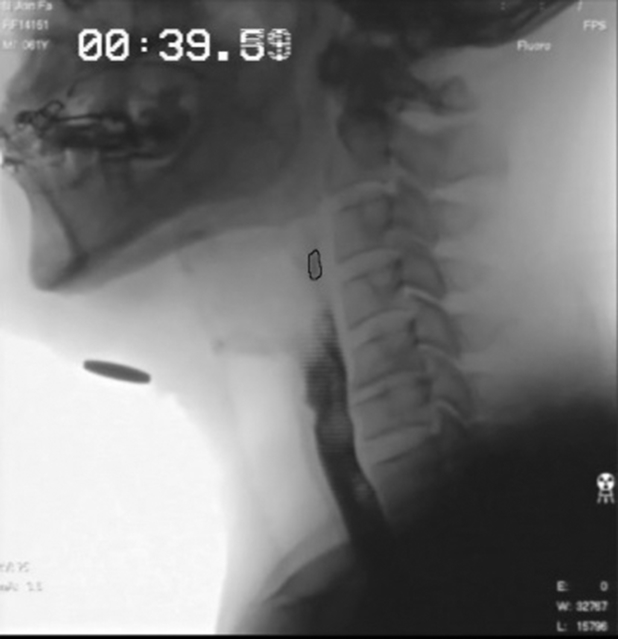

Fig. 2.

The beginning of the pharyngeal phase of swallowing.

Fig. 3.

The end of the pharyngeal phase of swallowing. The time between Figs. 2 and 3 is the pharyngeal transit time.